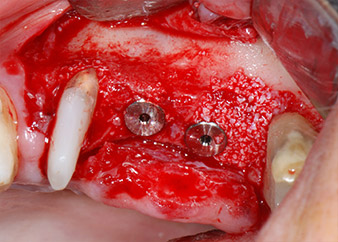

One month later, on the day of surgery, pain and inflammation at tooth 24 were minimal, but mobility of Miller class 2 was still present. After opening the flaps and cleaning the periapical and peri radicular infected tissue, the extent of the bone defect became obvious (Figs. 2 and 3).

total loss of bone and attachment

Fig. 2 and 3: After raising flaps, one month after endodontic revision and initiation of full-mouth periodontal therapy, the buccal root of tooth 24 showed a total loss of bone and attachment.